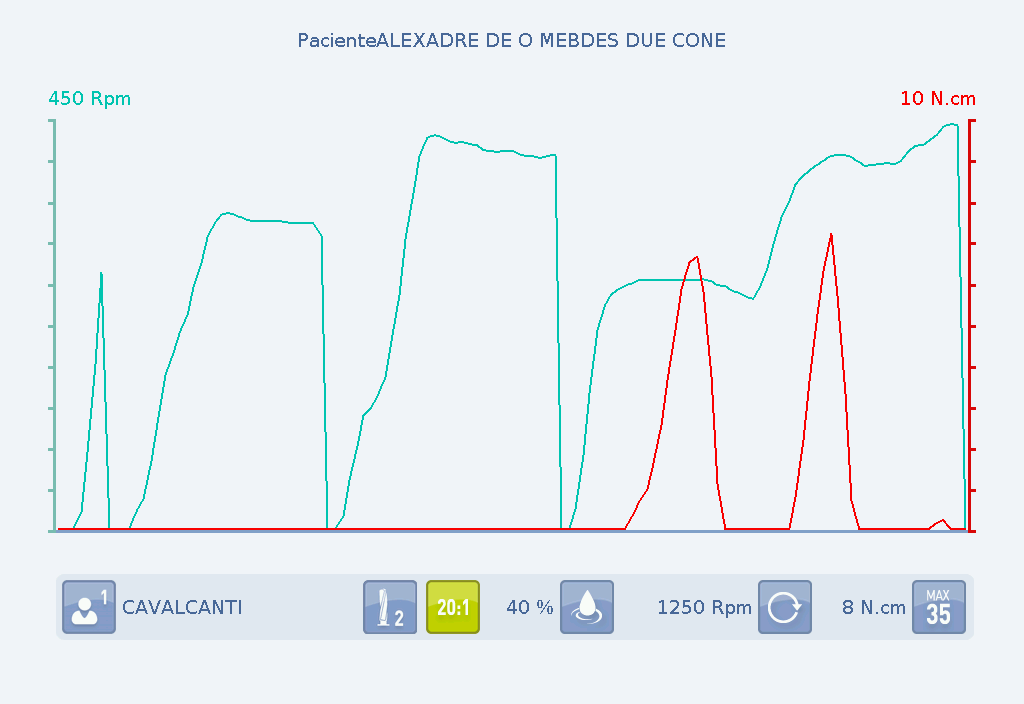

Alguns motores permitem medir tanto o torque utilizado sobre as brocas para o preparo do leito cirúrgico (osteotomia), bem como o torque de instalação, dando total controle da força empregada na broca e na inserção do implante, além da velocidade aplicada.

Gráfico A: Velocidade e torque durante o preparo do leito cirúrgico.